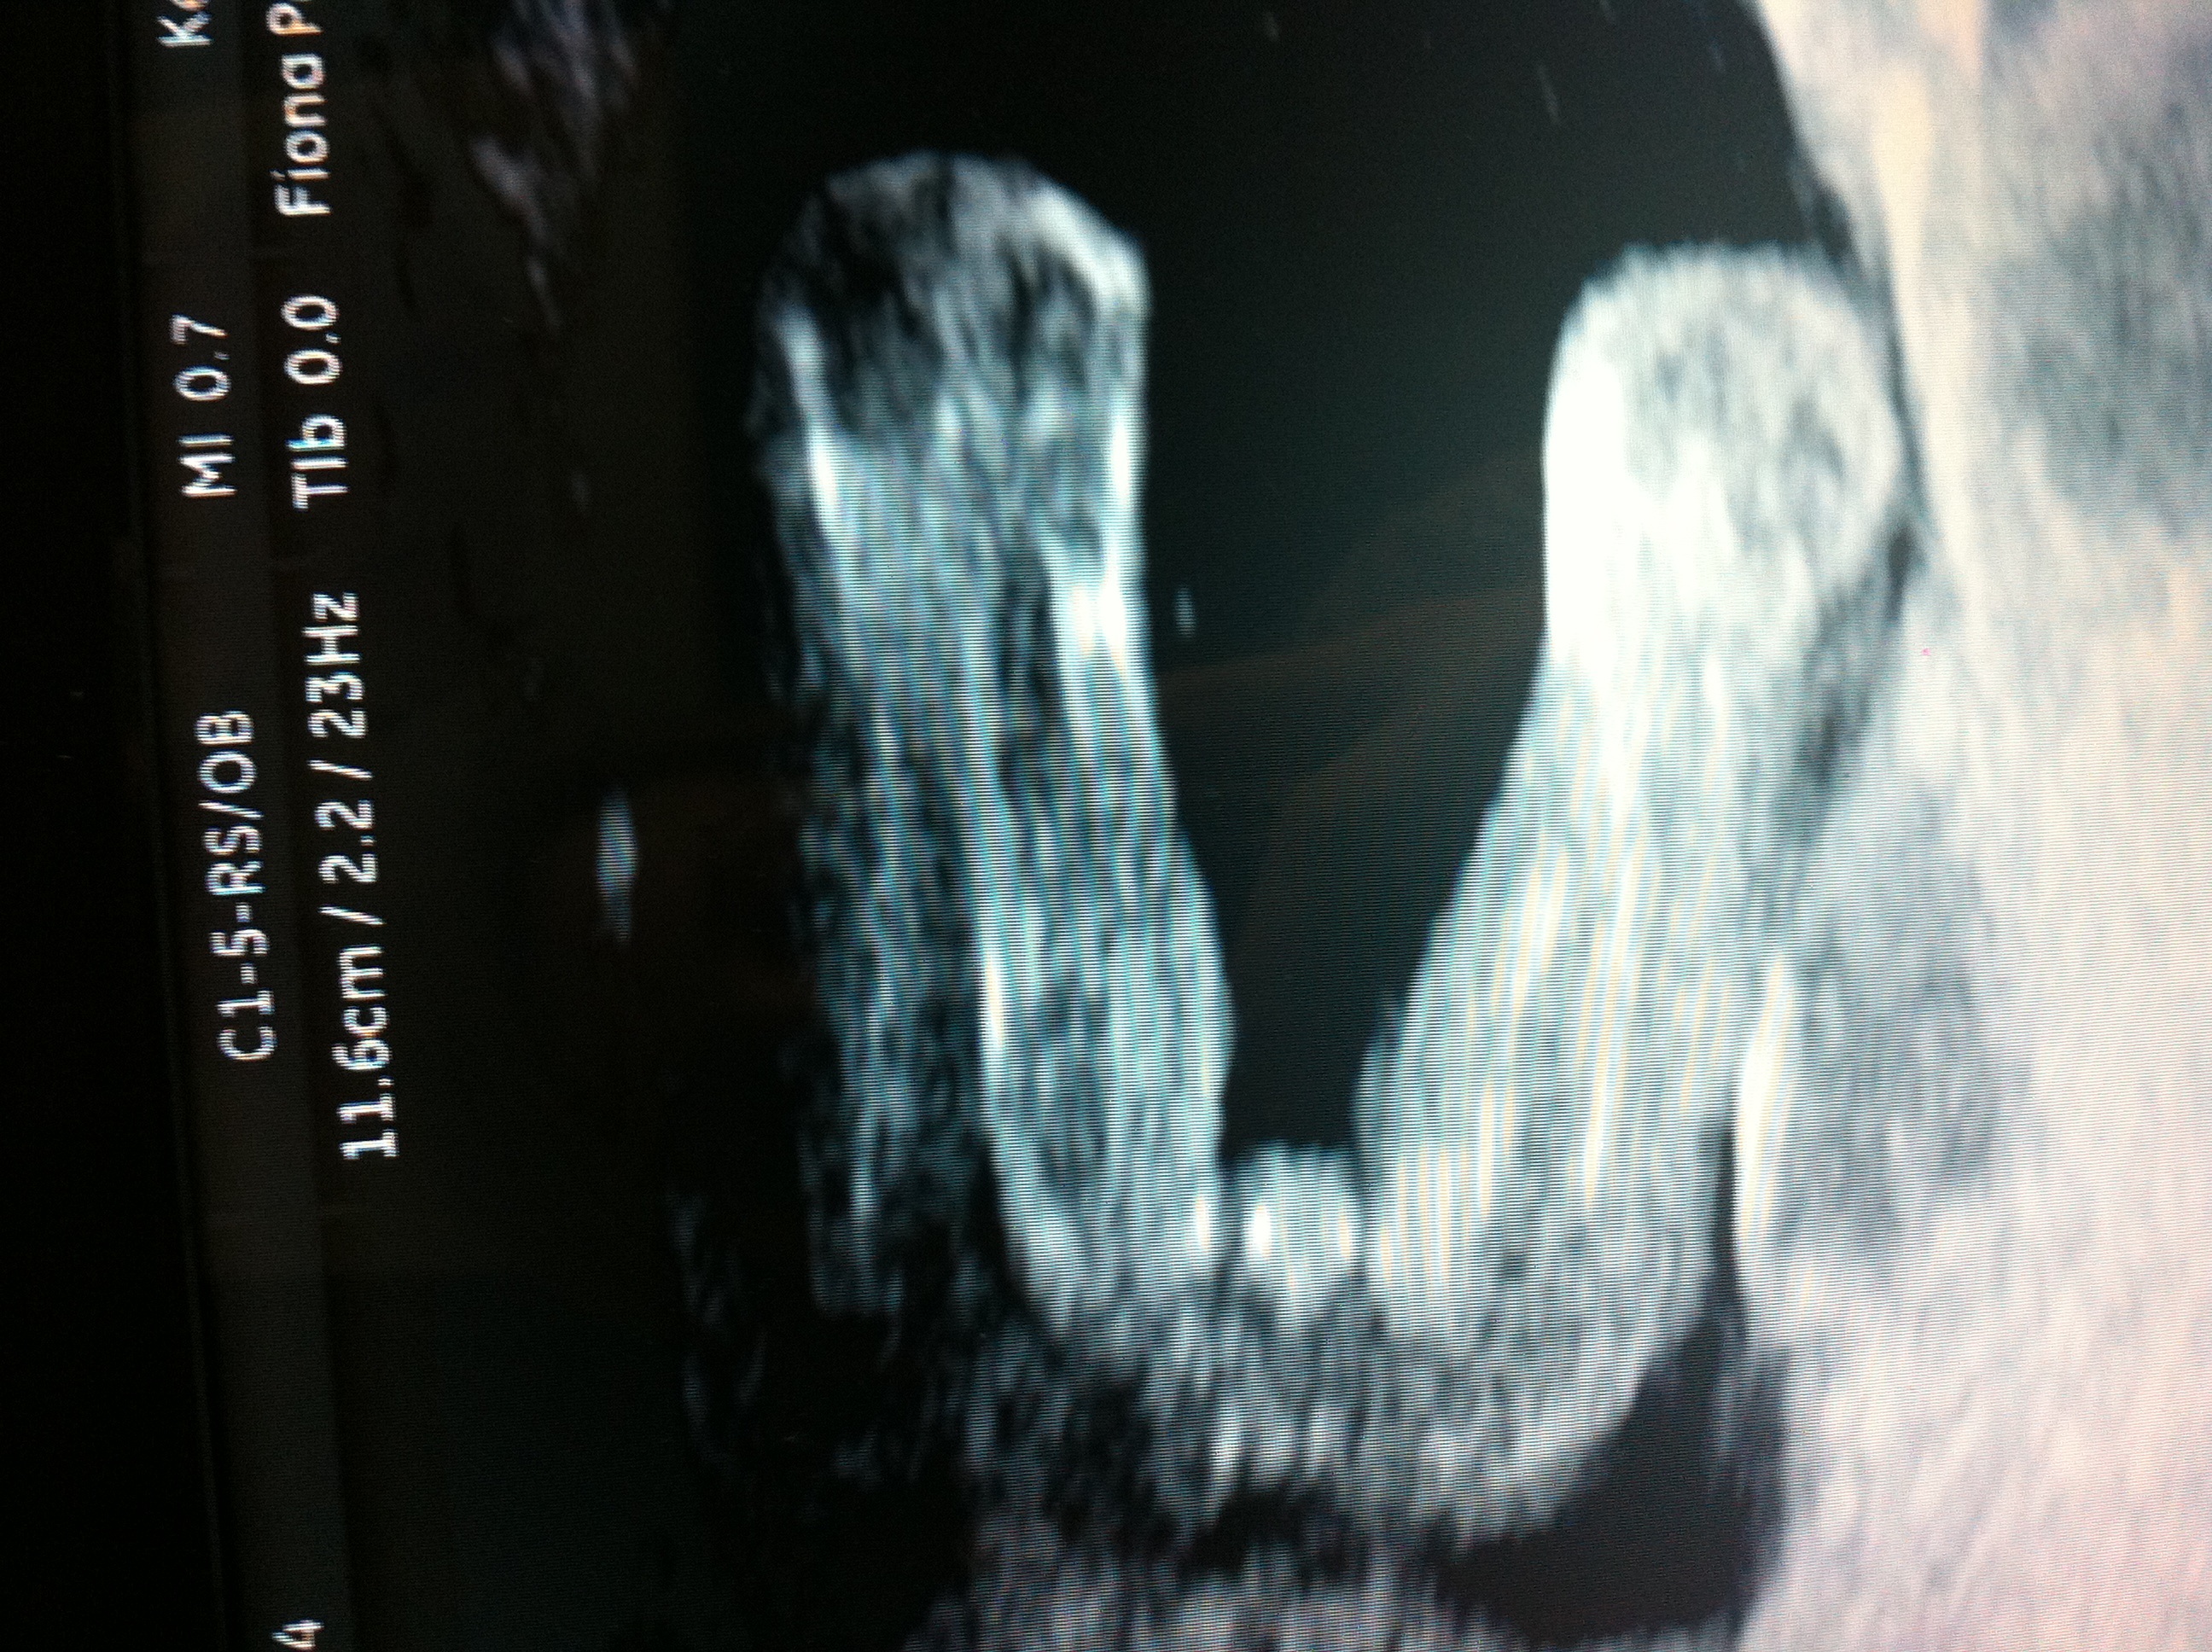

I had mine today and the lady said as far as she can see its a girl, I saw three lines but at one point I saw something sticking out! Would it be obvious if it was a boy? Is it pretty accurate to tell at this point? Attachment 14918Attachment 14919

I want a girl so badly I just hope it's correct x